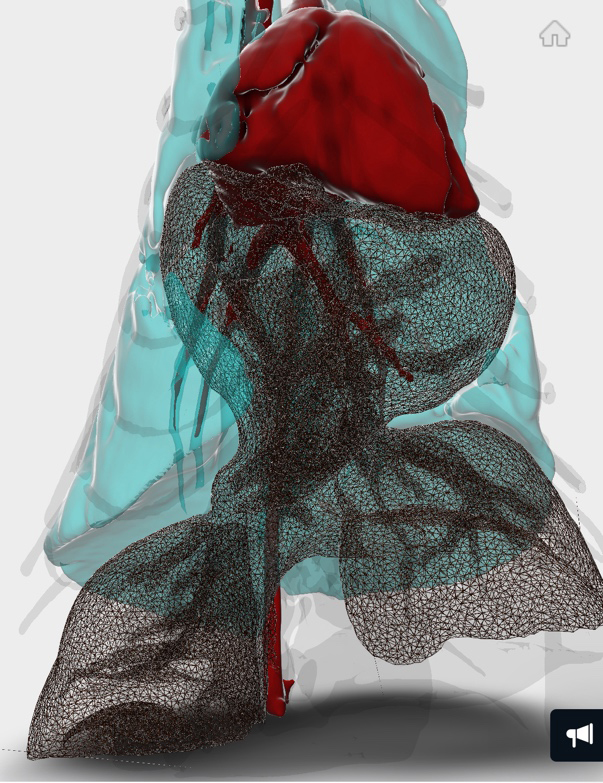

CT検査のデータを3D画像化し肝臓等の逸脱具合を確認